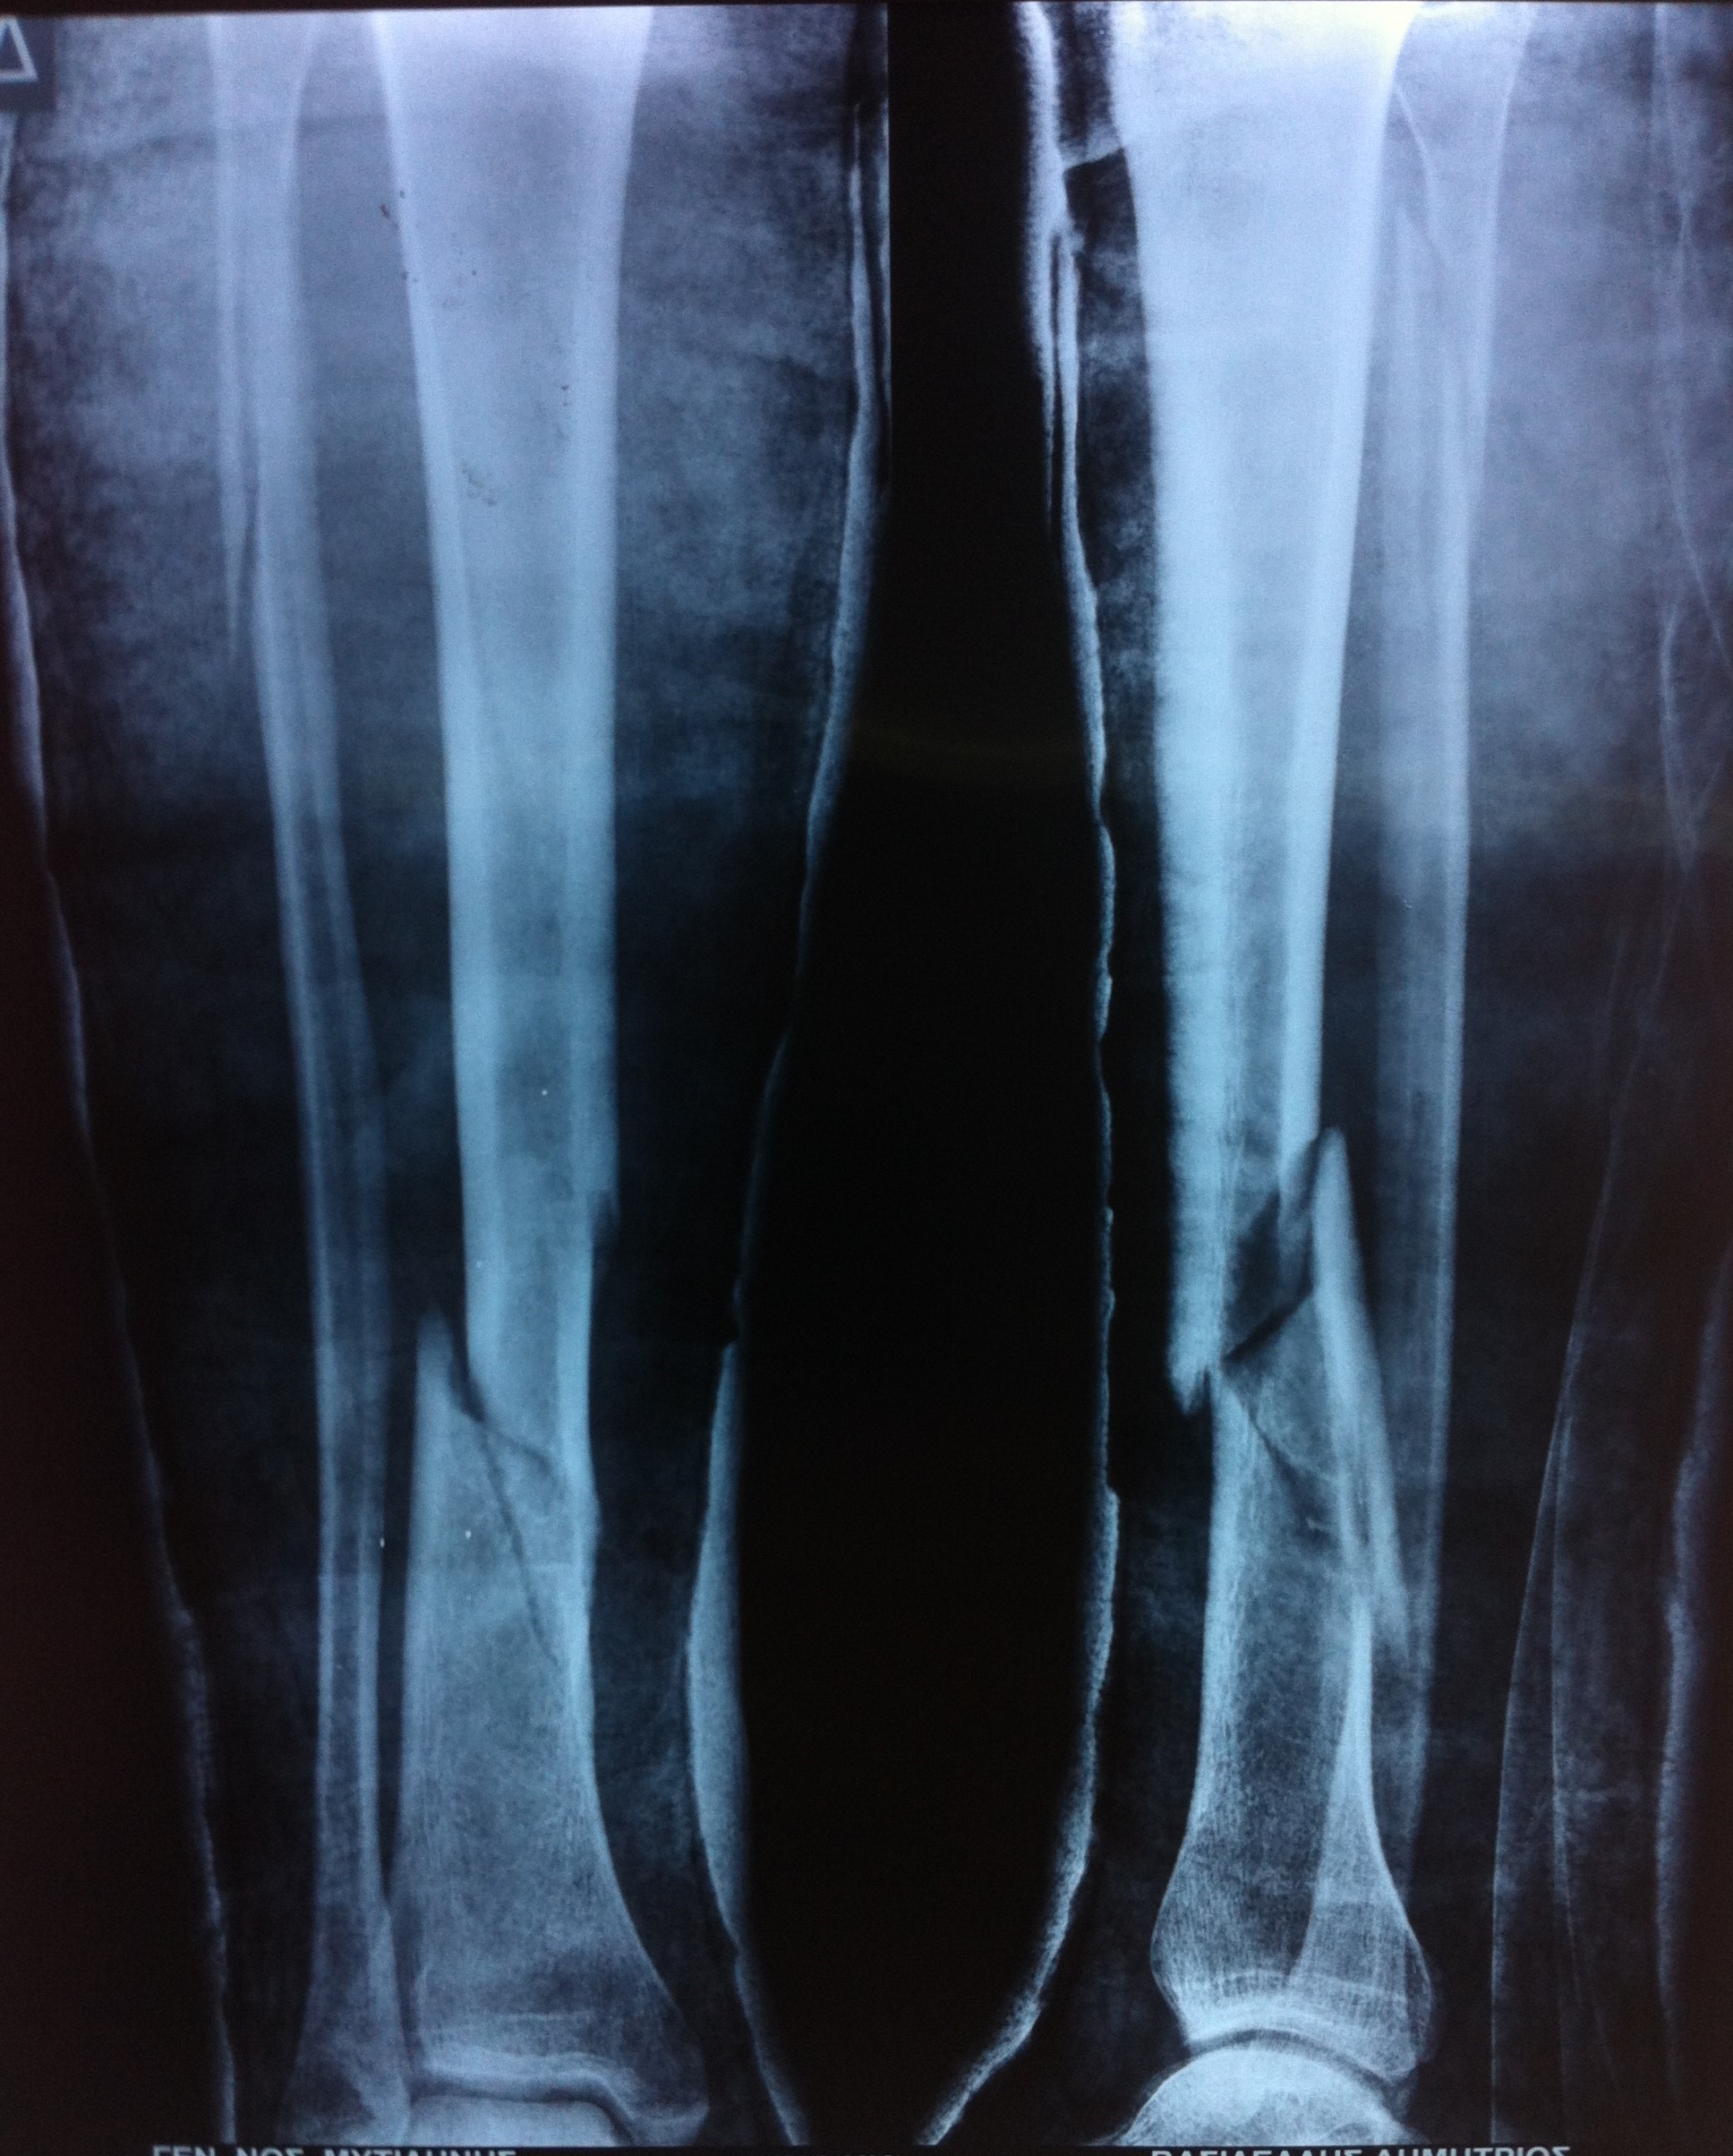

Ως κάταγμα κνήμης ορίζεται οποιοδήποτε διακοπή στην συνέχεια του οστού της κνήμης, είτε αυτή είναι ένα απλό ράγισμα (ρωγμώδες κάταγμα), είτε αυτή είναι μια εκτεταμένη συντριβή (συντριπτικό κάταγμα). Το κάταγμα κνήμης είναι ένα από τα συχνότερα κατάγματα. Πολλές φορές συνοδεύεται από κάταγμα της περόνης.

Η διάγνωση του κατάγματος κνήμης πραγματοποιείται μετά από μια επίσκεψη σε έναν έμπειρο ορθοπαιδικό. Σε πρώτο στάδιο η λήψη ενός λεπτομερούς ιστορικού και η κλινική εξέταση του ασθενούς είναι απαραίτητα για την διάγνωση. Στη συνέχεια, ο ασθενής υποβάλλεται σε απεικονιστικό έλεγχο με απλές ακτινογραφίες και σε κάποιες περιπτώσεις με αξονική ή/και μαγνητική τομογραφία. Οι απεικονιστικές εξετάσεις δίνουν σημαντικές πληροφορίες για τον τύπο του κατάγματος, που είναι απαραίτητες για τον καθορισμό της μετέπειτα θεραπείας.